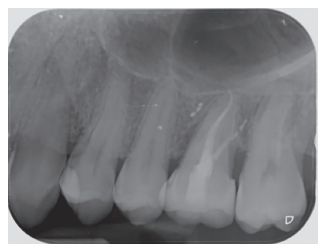

Tras rebajar la oclusión, se dio un punto en cruz con sutura monofilamento (Aragó®, Barcelona, España) alrededor del diente trasplantado para aumentar su fijación (Figura 13), realizándose una radiografía periapical intraoperatoria con técnica de paralelismo (Figura 14).

Transcurridos 2 meses se realizó una nueva revisión clínica (Figura 17) y radiográfica mediante radiografía periapical (Figura 18), procediéndose a retirar la ferulización. A los 3 meses se realizó otra revisión clínica (Figura 19) y radiográfica mediante radiografía periapical paralelizada (Figura 20), donde se puede observar una adecuada formación ósea alrededor del diente trasplantado.

Los estudios clínicos publicados evalúan clínica y radiográficamente a los pacientes, mediante radiografías periapicales9,10,12,15,17,18 o mediante periapicales y radiografía panorámica4,13,14. En la radiografía periapical se pueden apreciar la presencia de áreas radiolúcidas, reabsorciones radiculares externas e internas, anquilosis y el estado de desarrollo radicular18, siendo fundamentales en la evolución de esta modalidad terapéutica. En el presente caso clínico se apreció de manera radiográfica un área radiolúcida alrededor del diente, que fue modificándose con el paso del tiempo, para conseguir una densidad ósea similar del hueso en contacto con el diente trasplantado, en comparación al hueso circundante. Asimismo, no se apreciaron lesiones apicales ni presencia de reabsorciones radiculares durante el tiempo de seguimiento.